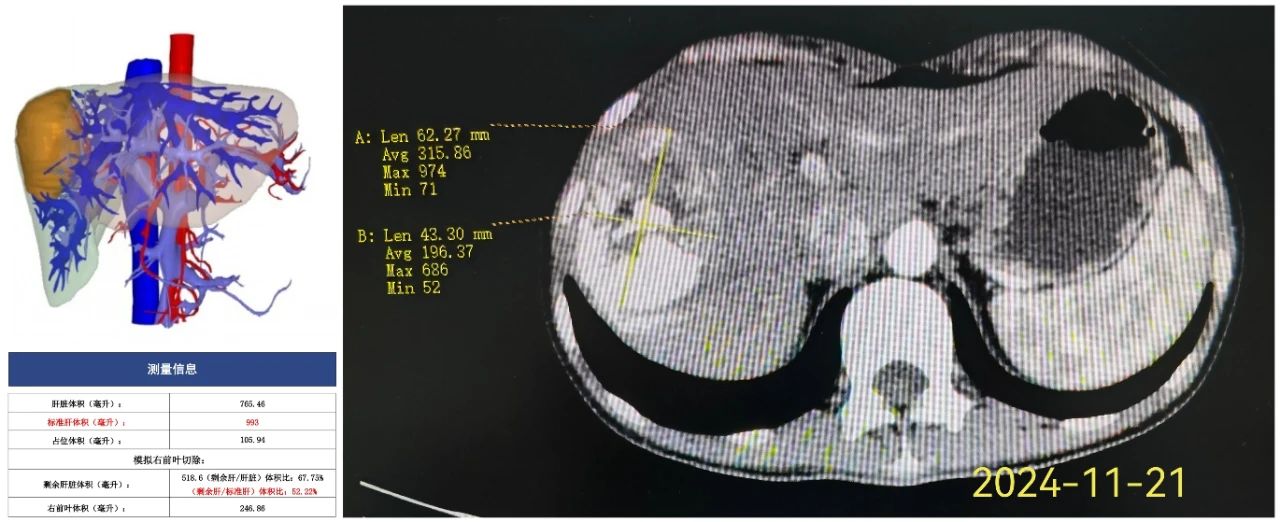

经过多学科讨论,先行介入栓塞及靶向免疫治疗(TACE+安罗替尼8mg、派安普利单抗 200mg)。一月后评估肿瘤较前缩小。经过3程转化治疗,肿瘤明显缩小,左肝较前增大,腹部增强CT示较大截面大小约63mm×43mm×76mm。再行三维重建,评估剩余肝体积约达52%。